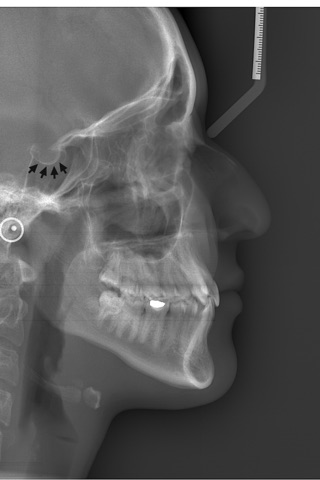

If so, this app will help you to judge, diagnose and practice from X-rays by bringing together all these real patient cases as a digital library.

Oral Radiology App is designed as a reliable learning tool for oral and maxillofacial radiology and created by the experts of the field. This data is tested and filtered several times. Perfectly simplified and clean information!